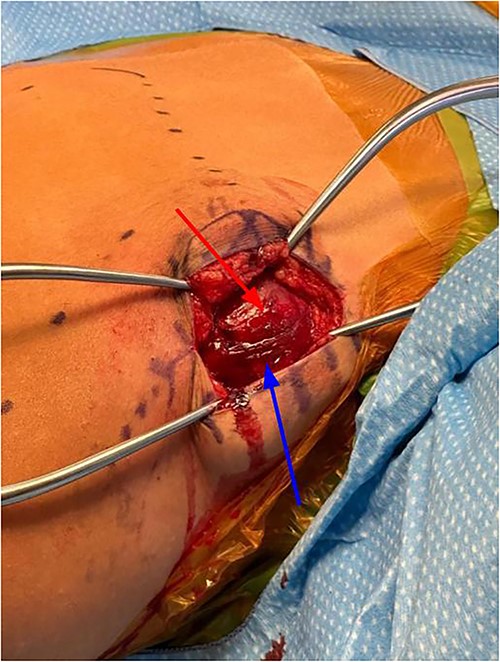

The patient was placed in the prone position on the operating table. The entire right upper extremity was draped including the entire right scapula area (Fig. 2). Fluoroscopy was used to identify the lesion and mark our planned surgical incision. A 5-cm transverse incision was made along the superior aspect of the bony lesion in line with the underlying trapezius muscle fibers.

Subcutaneous tissue was divided with the electrocautery. Investing fascia over the trapezius was identified and the division between the superior and middle fibers of the trap was identified. The raphe between the superior and middle fibers was then bluntly spread in line (Fig. 3). We then encountered the superior aspect of the ventral lesion on the scapula (Fig. 4). Of note, the majority of levator scapulae fibers were medial to this lesion; however, the most lateral portion of the muscle was overlying the lesion. These lateral fibers were spread in line to expose the pedunculated mass. Blunt dissection was then taken circumferentially around the stalk of the mass to ensure all soft tissue had been freed from the area (Fig. 5). An osteotome was then carefully placed within the wound at the base of the stalk, and the tumor was then removed and sent to pathology for analysis. The stalk remnant was then filed down to a smooth and stable base with a rasp without any significant areas of potential irritation or prominence. The wound was then copiously irrigated with normal saline. Fluoroscopy images demonstrated complete resection of the bony tumor. There was no active bleeding within the wound. The fascia overlying the trapezius muscle and the skin were then closed.

Exposure after superficial dissection, middle trapezius fibers (top arrow) and superior trapezius fibers (bottom arrow).